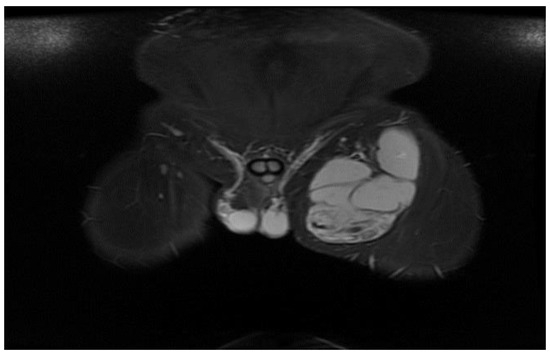

The MRI examination was performed on two patients for surgical purposes, to establish the relationship with other organs or vital structures and to guide the indication and the surgical plan. It is important to note the case of a 32-year-old male patient, hospitalized for the presence of a tumor formation at the base of the left thigh, in which the native and contrast enhanced MRI examination of the pelvis and thigh revealed: urinary bladder without parietal thickenings or endoluminal pathological processes; seminal vesicles without pathological signal changes; prostate measuring 4.7/3.2 cm, homogeneous, without pathological contrast plugs; without suspicious adenomegaly at the pelvic level; replacement process of polylobate space, which is relatively well demarcated, predominantly with fluid signal, multiple septate, without diffusion restriction, with gadophilia present at the peripheral and intralesional septal level, starting from the vicinity of the psoas and iliac muscle on the left side and extending into caudal direction through the anterior portion of the inguinofemoral region on the left side to the proximal region of the left thigh, and coming into contact with the common iliac, external iliac and femoral vessels on the left side (apparently with preserved flow at their level and with the apparently left femoral diaphysis but no macroscopic invasion phenomena at this level); previously described space-replacing process, which extends over a cranio-caudal distance of approximately 33 cm and shows inhomogeneous signal at the level of some of the intralesional cystic areas; deep to the gluteus maximus muscle on the left side, a relatively well-defined area can be seen, with a polylobate contour, multiple septa, with a similar appearance to the previously described space-replacing process, with dimensions of 2.9/2.75 cm—possibly parasitic cystic lesions (Figure 4, Figure 5, Figure 6, Figure 7, Figure 8 and Figure 9).

Figure 4.

STIR MRI sequence, coronal—Hydatid cyst with daughter cells present in the left thigh.